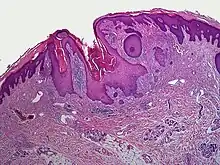

| Dilated pore of Winer |

A dilated pore, also known as a dilated pore of Winer, is a cutaneous condition characterized by a solitary, prominent, open comedo on the face or upper trunk of an individual.[1]: 675 Louis H. Winer is credited with discovering the dilated pore. [2][3]